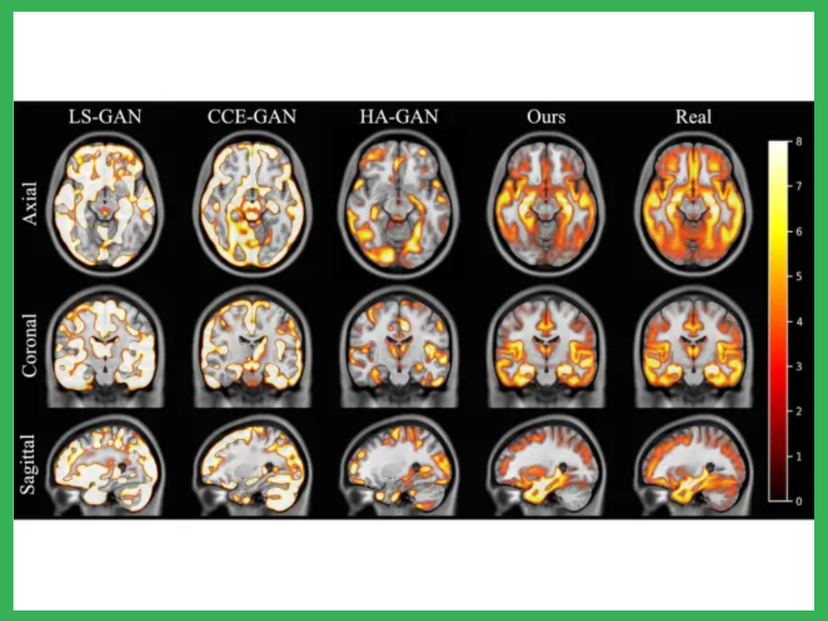

Image from study, showing areas of the brain affected by Alzheimer's disease in yellow, found when using real data compared with synthetic data. Synthetic data from KCL model is similar to the real images shown

Data produced by the model was realistic enough to replicate human anatomy. For example, the team showed that a dementia research study running on real data would show the same outcomes as a study running on generated synthetic data. By looking at large volumes of data, the AI model learned how age and sex affect the brain, and how pathologies impact anatomy.